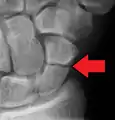

Radiolucency around a 12 days old scaphoid fracture that was initially barely visible.[13]